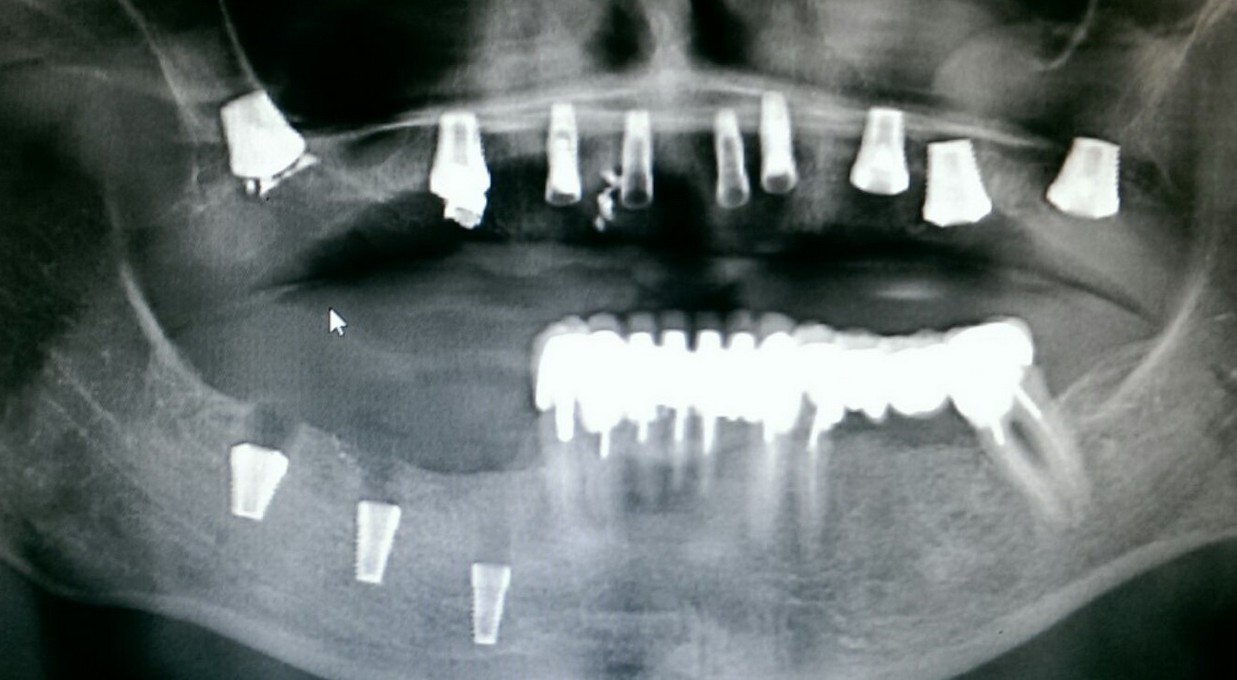

Cегодня я хотел бы показать вам одну работу, которую я начал более года назад. А заодно рассказать о ее нюансах. Вы знаете, что секретов у меня нет, поэтому буду рад вашим вопросам и ремаркам в комментариях

Цель имплантологического лечения — не воткнуть импланты так, чтобы они прижились, а создание надёжной и долговечной опоры под планируемую ортопедическую конструкцию.